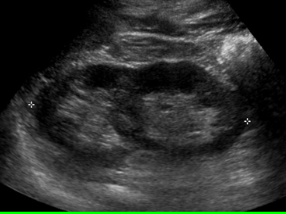

Crossed Ectopia

One kidney lies across the midline and is fused to the other kidney. Second most common fusion anomaly.

crossed ectopia image